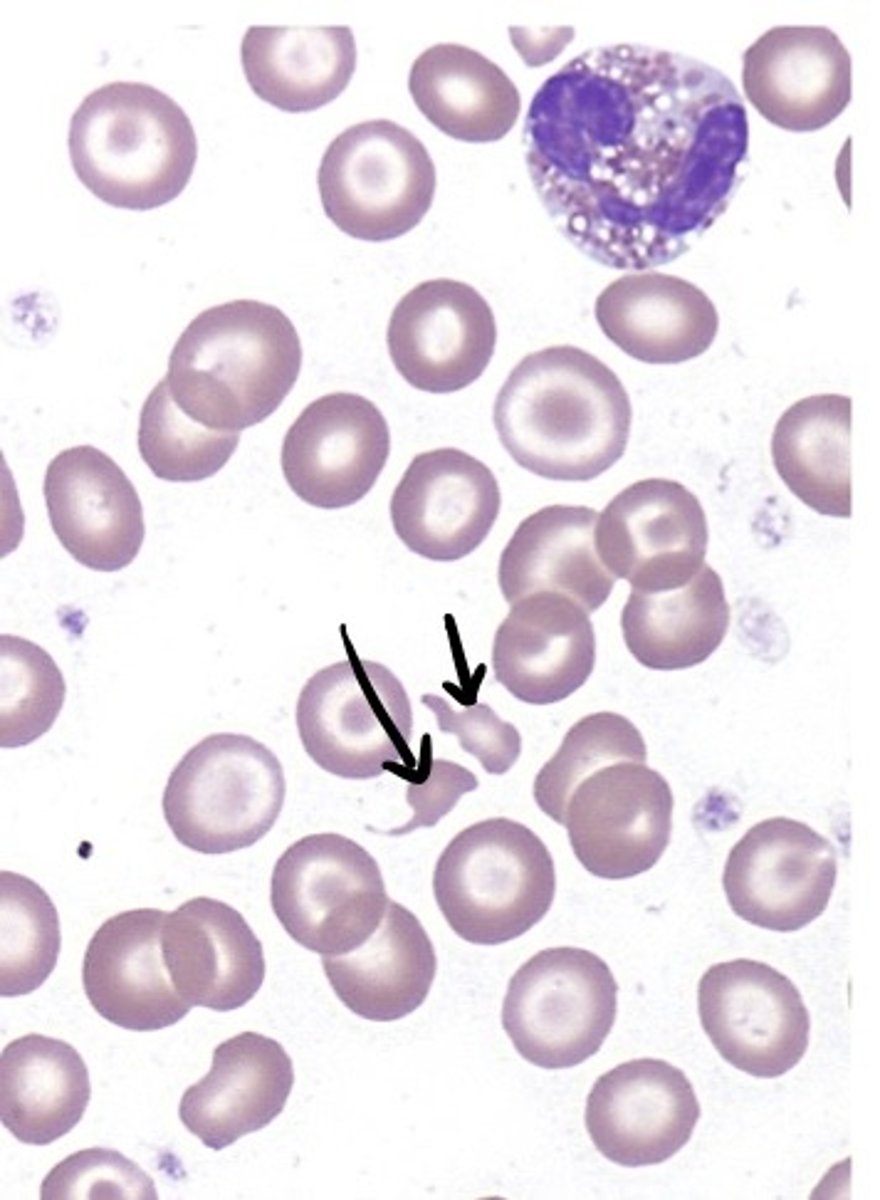

schictocytes

RBC fragments

keratocytes

one or 2 horn like projections